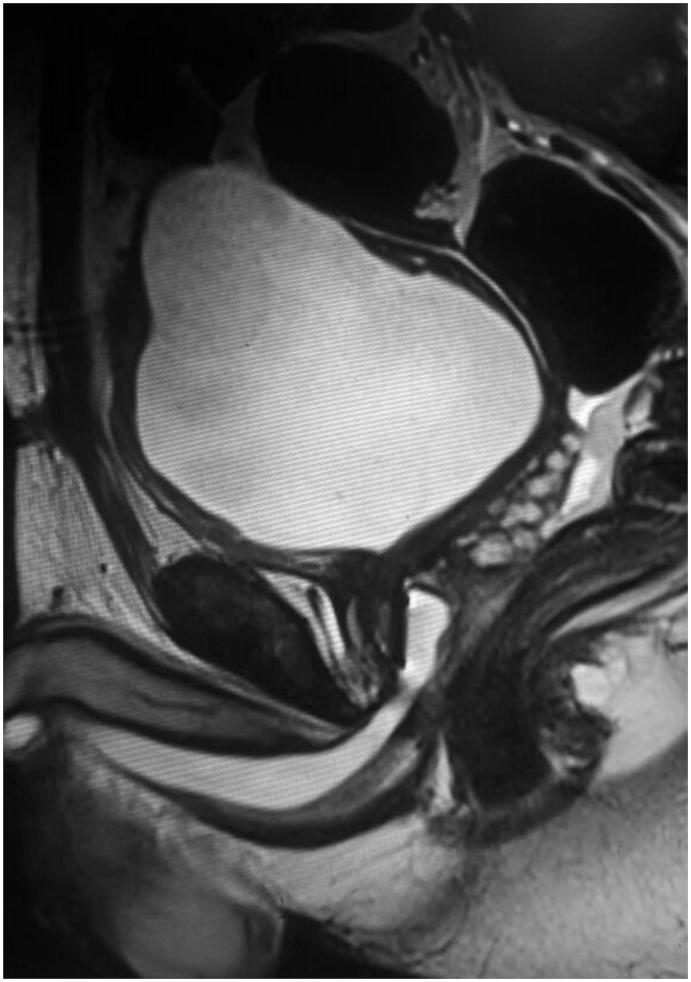

Post traumatic isolated bladder neck transection: Unreported and undescribed injury.

Urol Case Rep. 2017 Dec 9;17:67-69. doi: 10.1016/j.eucr.2017.12.001. eCollection 2018 Mar.